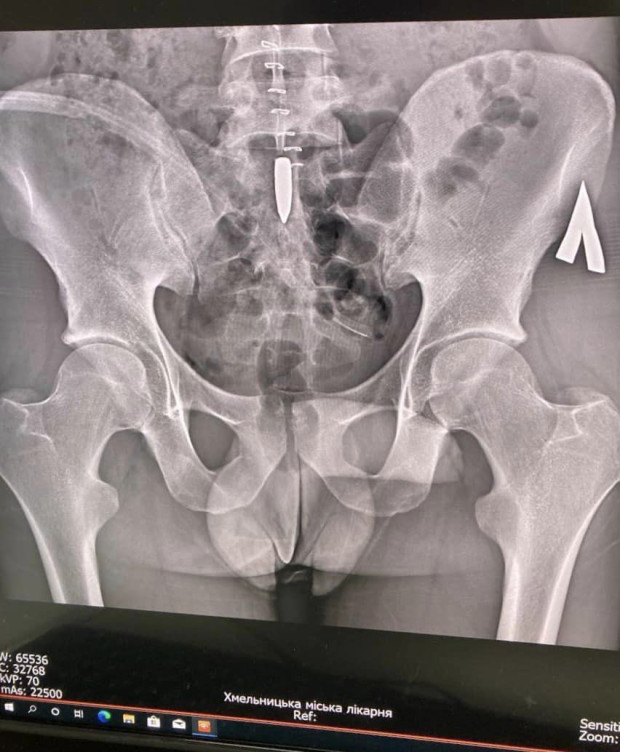

Куля через бічну черевну стінку зайшла та опинилась у попереково-крижовому відділі хребта, пробила тверду мозкову оболонку, поміняла траєкторію вниз, і опинилась на рівні 1-2 крижових хребців, між сакральними нервовими корінцями які відповідають за інервацію тазових органів та нижніх кінцівок.

фото: Хмельницька Міська Лікарня

" Першим етапом хірургами ХМЛ була проведена первинна хірургічна обробка вогнепального поранення бічної черевної стінки, із ушиванням дефектів внутрішніх органів. Після стабілізації пацієнта, нейрохірургами ХМЛ було проведено надскладне оперативне втручання: між сакральними корінцями виявлено кулю калібром 7.42, складність оперативного лікування в тому що куля у середені огорнута у так звану «біоплівку» в яку також були окутані нервові корінці, які виконуюють важливі неврологічні функції (описані вижче) розмір яких у діаметрі 1-2 мм, і мають дуже ніжну структуру, -розповіли лікарі.